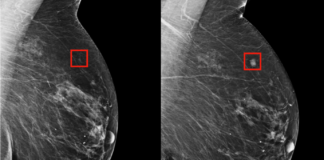

Yapay zeka meme kanserini radyologlar kadar etkili bir şekilde tespit edebiliyor. ,

Yapay zeka meme kanseri tespitinde başarılı oldu

İngiltere Lund Üniversitesi’nden bilim insanları, yapay zekanın tespit...